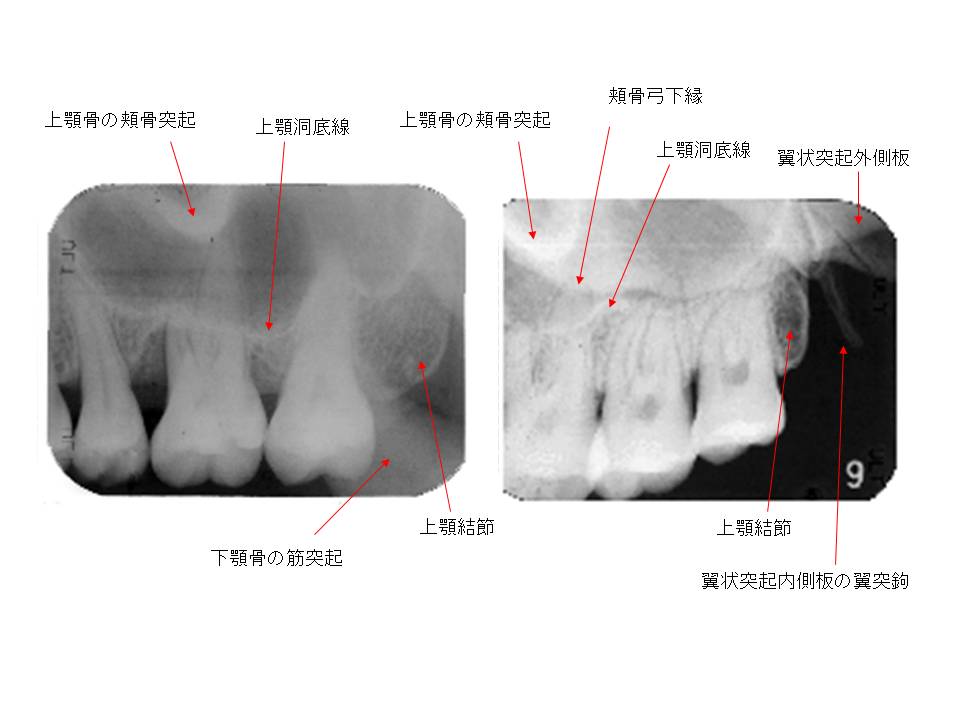

口内法(二等分法・咬合法)撮影の解剖